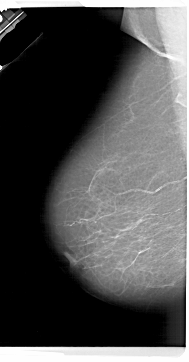

Могут наблюдаться три основных типа аномалий:

асимметричные плотности ,

масс (с анализом их форм, размеров и пограничных характеристик) и искажений архитектуры

кальцификации, для которых размер, количество, распределение, морфология и неоднородность должны быть детализированы.

Увеличительное стекло является очень полезным инструментом во время этого исследования. Женскую грудь можно схематически описать (см. Предыдущую страницу) как от 10 до 20 гландулярных конических лопастей, основание которых расположено на грудной мышце, а вершина - это сопло. Каждая лепесток сопровождается конъюнктивными структурами, среди которых жировая ткань.

Жировая ткань является радиопрозрачной: плотность обусловлена лобулярными и протоковыми элементами, а также волокнистыми опорными структурами. Маленькие протоки сходятся к ниппели.